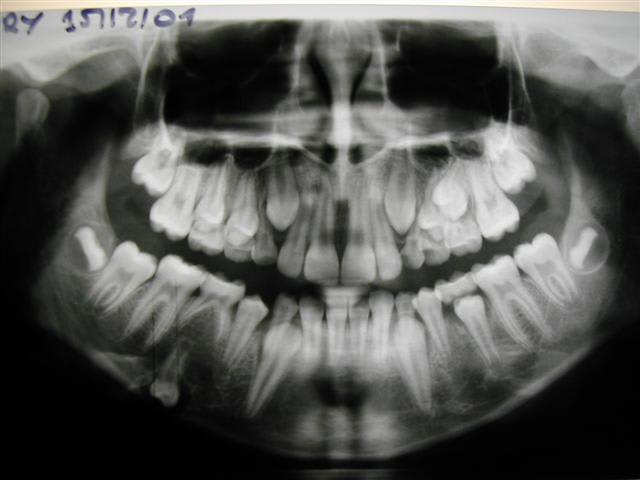

pano comme on a pu

la pano n'est pas passée

deuxième essai

la pano n'est vraiment pas terrible,mme le kyste je ne le discerne pas tant(mais où st donc mes lunettes)

par contre tout en bas ,les 2 images,sont les germes de 33 et 34,j'imagine

franchement je ne vois pas gd chose sur ta pano

tu ns en reposte une stp,vernal?

cependant lapadoué dire que la 74 est saine... euh... pas de carie ,d'accord mais au niveau des racines elles ne me semblent pas d'aspect normal

et puisque kyste il y a on peut s'interroger sur sa vitalité

après avoir trafiqué un peu la pano pr mieux voir,je pensais ext de 73 et 74 sous AG (mais ds un service pedo) à cause du curetage du kyste:il me semble trop important,trop bas et la cicatrisation à cet âge trop rapide pr permettre un drainage naturel suffisant

puis attente 6 mois pr voir l'evolution des germes,l'angulation de 33 laissant préjuger qu'elle va peutêtre demander traction

je remets ta pano un peu retravaillée sur photoshop